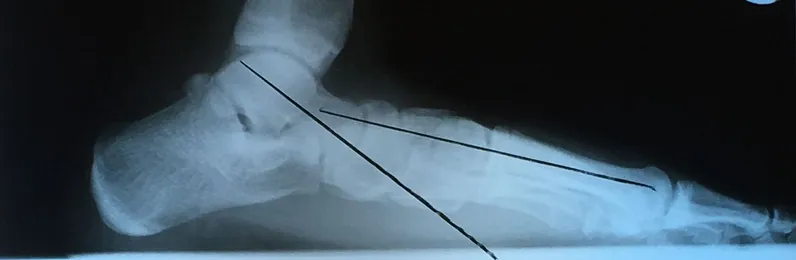

Pre and Postop X-rays Subtalar Joint Implant (Below)

Patient JD